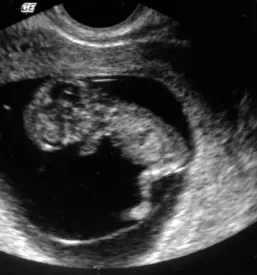

V naši ambulanti se predvsem trudimo, da bi imeli čimbolj profesionalen, diskreten in strokoven pristop k problematiki, ki jo obravnavamo. Da pa bi našim pacientkam zagotovili le najboljše, se nenehno izobražujemo in skušamo dosledno slediti sodobnim smernicam, ki se izoblikujejo tako pri nas kot tudi v tujini. Zato je med drugim na voljo tudi 3d 4D UZ - oziroma ultrazvočni pregled ploda.

V sklopu svoje ambulante ponujamo ginekološko in porodniško dejavnost, poleg tega svojim pacientkam nudimo preglede dojk in različne oblike ultrazvoka. Samoplačniško izdelamo tudi 3D 4D UZ.